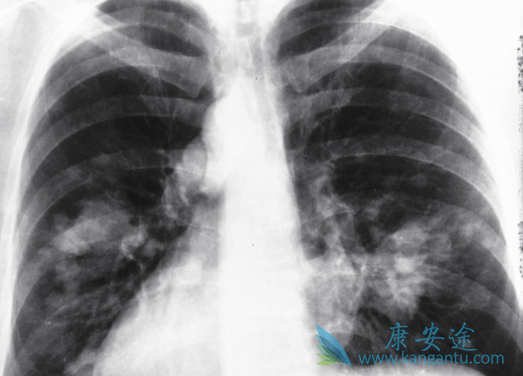

近期,一项临床试验研究了吉非替尼(GEFITINIB)对非小细胞肺癌患者免疫功能的影响,研究发现,EGFR-TKI靶向治疗非小细胞肺癌,可明显改善患者的免疫功能,临床疗效较好,不良反应发生率低。该文章发表于《中国临床药理学杂志》上。该研究旨在观察表皮生长因子受体酪氨酸激酶抑制药(EGFR-TKI)吉非替尼在靶向治疗非小细胞肺癌(NSCLC)中对患者免疫功能的影响。

研究者们入选65例服用吉非替尼(GEFITINIB)治疗的非小细胞肺癌患者,所有患者均口服吉非替尼250mg,连续服用30d。观察治疗前1周、治疗后1,3,6个月T淋巴细胞亚群和自然杀伤(NK)细胞的变化,观察治疗后的临床疗效及不良反应发生情况。结果显示,治疗后客观缓解率为75.38%。